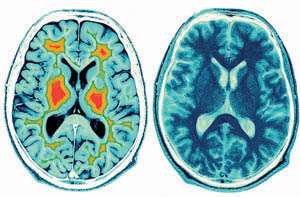

At this point, the findings suggest a measurable benefit that people could achieve through body-mind meditation, especially involving an effective training regimen. Posner and Tang plan to study American undergraduates with functional magnetic resonance imaging to examine brain network changes induced by training during attention tests.